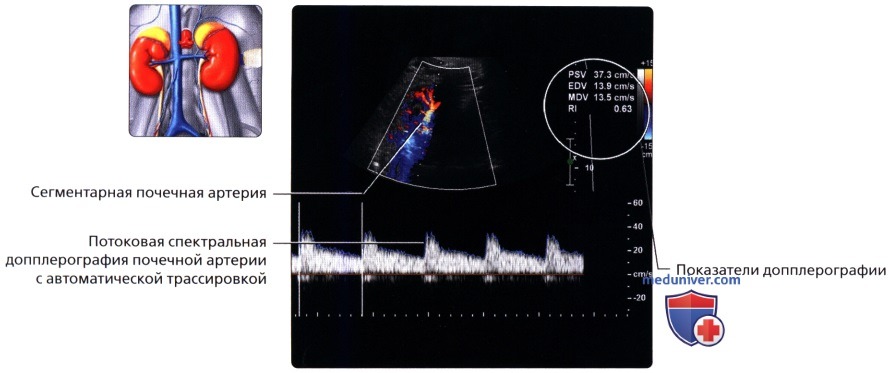

Неотъемлемой частью обследования почек стало ультразвуковое допплерографическое исследование, дающее возможность наблюдать за кровотоком в почечных сосудах. Делая УЗИ сосудов почек, можно установить на ранней стадии стеноз артерий, сбои в кровоснабжении, сосудистые сбои.

УЗДГ (УЗИ сосудов почек) выполняется в положении больного лежа на боку или сидя. Каких-то особенностей у этой процедуры нет. Врач также перемещает датчик по поверхности кожи пациента, внимательно изучая постоянно меняющиеся на мониторе изображения.

Ультразвуковое исследование при заболеваниях сосудов почечного кровообращения

К этим заболеваниям относятся поражения почечной вены и артерий. Это могут быть сужения (стенозы), закупорка тромбом (тромбозы), а также нарушение целостности сосудов при травмах.

| Патология | Цель назначения УЗИ | Ультразвуковые признаки |

| Тромбоз почечной вены | Цель при ультразвуковом исследовании сосудов одна и сводится в первую очередь к тому, что необходимо определить тип и калибр пораженного сосуда. На втором этапе необходимо обнаружить зоны с кровоизлияниями и инфарктом почки и оценить степень поражения. | На первой стадии болезни на УЗИ видна увеличенная почка со сниженной эхогенностью по периферии (в корковом веществе). Через 1 – 2 недели периферия становится эхогенной. Иногда из-за очаговых кровоизлияний появляются небольшие гипоэхогенные участки. При помощи допплерографии выявляется снижение или отсутствие кровотока в почечной вене. Если развивается «обходной» венозный кровоток, то эхогенность возвращается к норме, однако почка может уменьшиться в размерах. |

| Тромбоз почечной артерии | Когда поражена одна ветвь почечной артерии, на УЗИ виден эхогенный неоднородный участок, который переходит в гипоэхогенный в течение нескольких дней. Если тромб находится в основном стволе почечной артерии, то вначале почка увеличена в размерах. При длительном отсутствии кровоснабжения почка атрофируется и уменьшается в размерах, становясь гипоэхогенной. Окончательный диагноз ставится на основе результатов допплеровского исследования. При допплерографии отмечается снижение или отсутствие кровотока в артерии с тромбом. | |

| Стеноз почечной артерии | Зоны инфаркта почки на УЗИ визуализируются как гипоэхогенные треугольные участки в паренхиме. Когда зоны инфаркта замещаются соединительной тканью (рубцом), на УЗИ они становятся гиперэхогенными. |